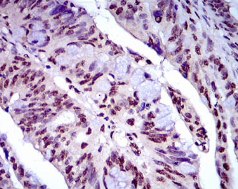

NAPSA Mouse Monoclonal antibody[10C4B]

The activation peptides of aspartic proteinases plays role as inhibitors of the active site. These peptide segments, or pro-parts, are deemed important for correct folding, targeting, and control of the activation of aspartic proteinase zymogens. The pronapsin A gene is expressed predominantly in lung and kidney. Its translation product is predicted to be a fully functional, glycosylated aspartic proteinase precursor containing an RGD motif and an additional 18 residues at its C-terminus.

Immunogen:    Purified recombinant fragment of human NAPSA (AA: 20-158) expressed in E. Coli.

IHC    1/200 - 1/1000